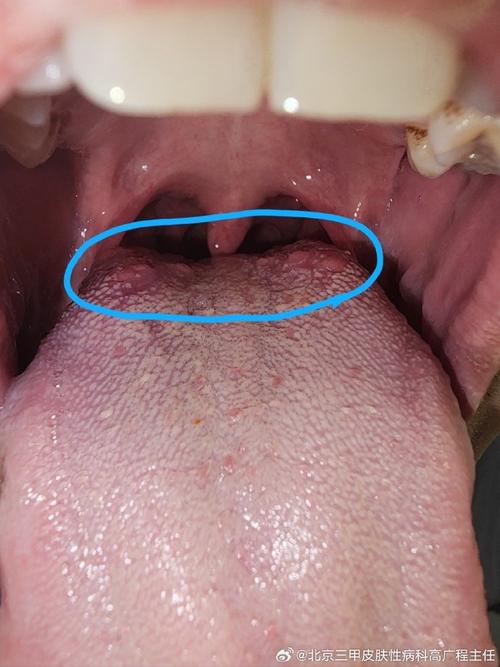

舌根起泡是口腔溃疡吗?怎么快速好?

舌根起泡、像溃疡的感觉,可能由多种原因引起,我们来分析一下最常见的一些可能性,以及您可以如何应对。

- 外观:起初是一个或多个小红点或小水泡,很快会破溃,形成圆形或椭圆形的浅表溃疡,表面有黄色假膜,周围有红晕。

- 位置:可以发生在口腔任何黏膜,包括舌根、舌侧、颊黏膜等。

- 簇集性水疱:不像单个溃疡,通常是成簇的小水泡,然后破溃形成多个小溃疡。

- 外观:是一个充满血液的、半球状的大疱,颜色为深红色或紫红色,疱壁较薄,容易破裂,破裂后会留下一个边缘不规则的、鲜红色的出血创面,疼痛感明显。